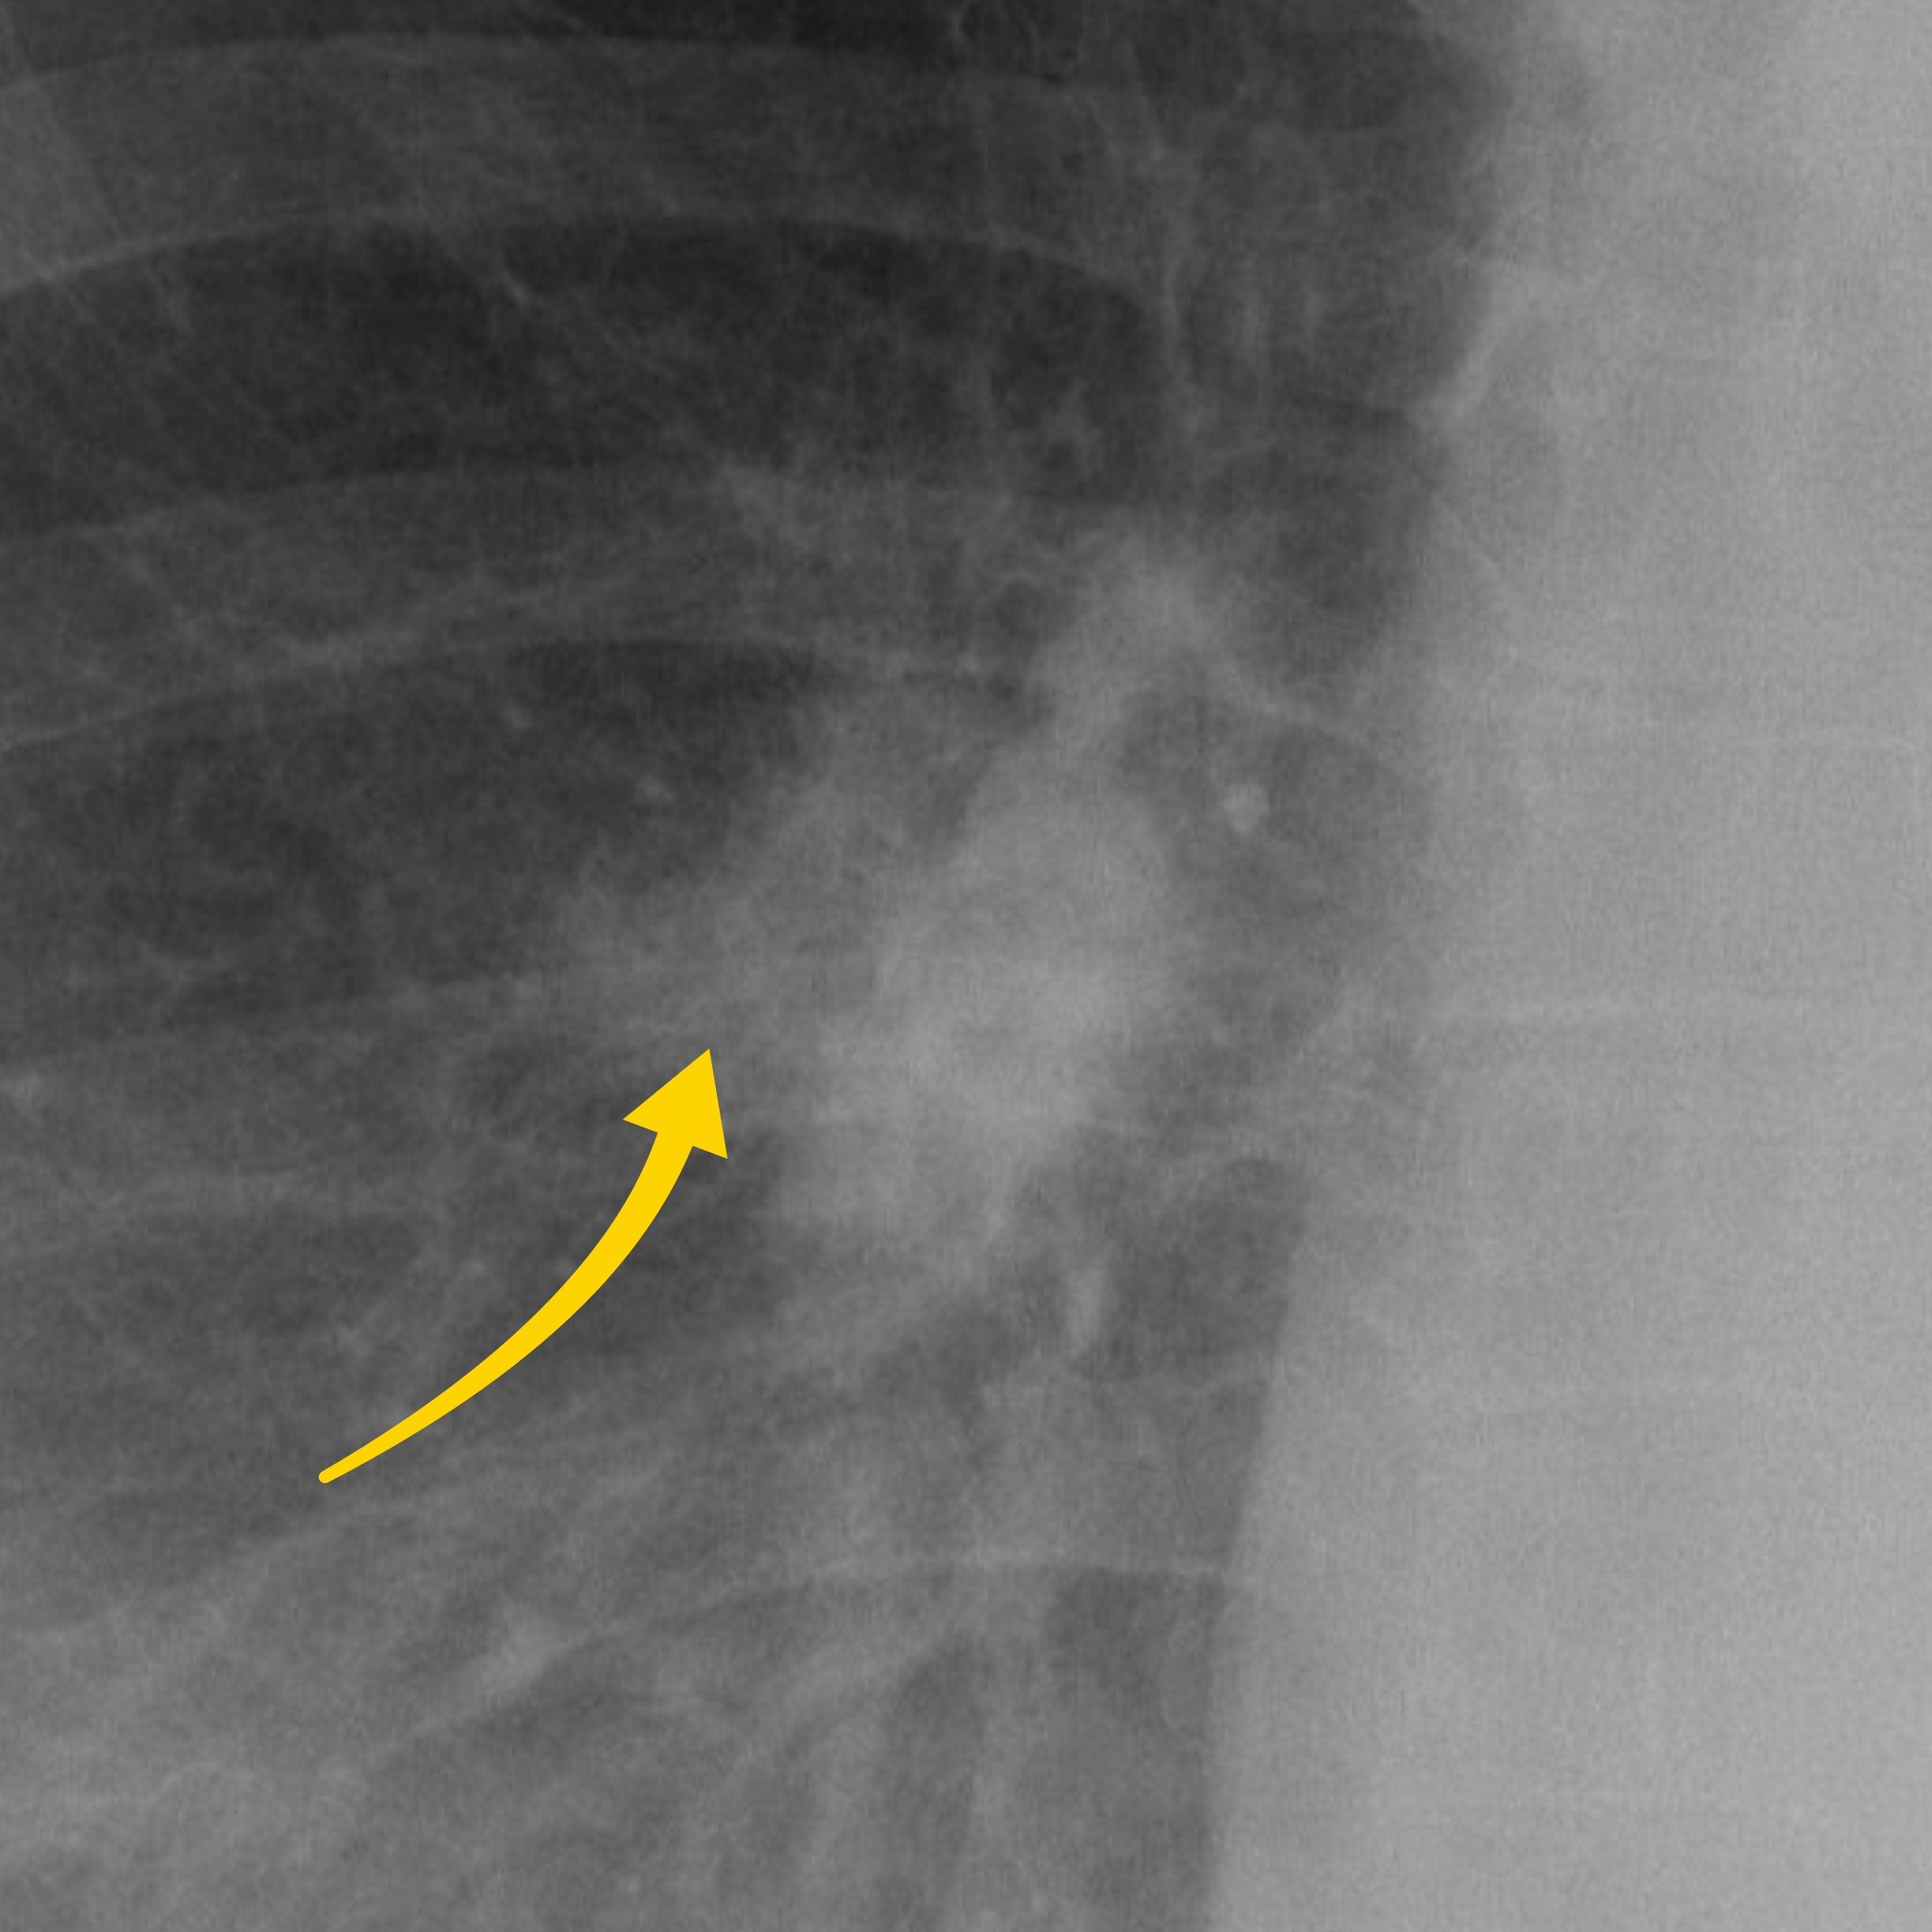

Case 1

A female in their 60s presents with unremitting cough on a background of weight loss. Have a look at the chest X-Ray below:

What is the most likely diagnosis? Choose from one of the following: